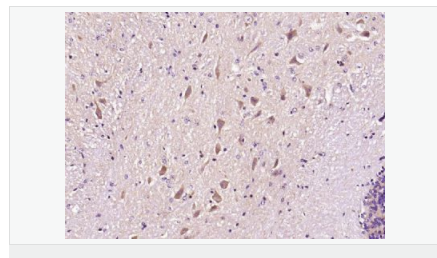

| 產品應用 | WB=1:500-2000 ELISA=1:5000-10000 IHC-P=1:100-500 IHC-F=1:100-500 Flow-Cyt=1ug/Test IF=1:100-500 (石蠟切片需做抗原修復) not yet tested in other applications. optimal dilutions/concentrations should be determined by the end user. |